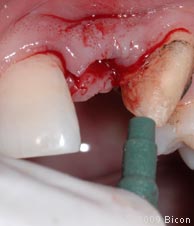

29. Удаление излишков мягких тканей, которые могут препятствовать правильной установке трансфера, производится посредством слепочного римера размером 3 мм, вращаемого вокруг направляющего штифта.